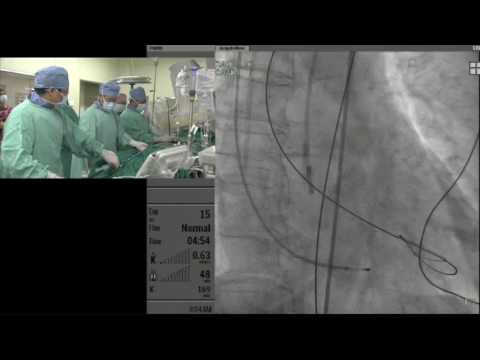

AP VALVES 2016_Live Case Session I